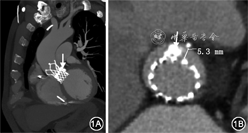

患者男性,71岁,主因“活动后呼吸急促3年,再发加重2周”于2019年12月19日入院。患者3年前出现活动后呼吸急促,休息数分钟可自行缓解,无胸痛、心悸、晕厥等症状,多次因夜间阵发性呼吸困难伴下肢水肿于当地医院住院治疗,诊断考虑“心脏瓣膜病,重度主动脉瓣狭窄”,给予药物保守治疗。2019年3月患者因上述症状加重于我院住院治疗,经胸超声心动图(TTE)结果显示:主动脉瓣二叶瓣畸形,重度主动脉瓣狭窄[主动脉瓣峰值流速5.7 m/s,平均跨瓣压差58 mmHg(1 mmHg=0.133 kPa)],轻中度二尖瓣反流,轻中度三尖瓣反流,舒张期左心室内径6.8 cm,左心室射血分数40%。实验室检查:N末端B型利钠肽原(NT-proBNP)10 972 ng/L(正常值范围:0~125 ng/L)。冠状动脉CT血管成像(CTA)检查排除冠心病。入院诊断:先天性主动脉瓣二瓣化畸形,重度主动脉瓣狭窄伴关闭不全,慢性心力衰竭,纽约心脏病协会(NYHA)心功能Ⅳ级。2019年3月6日行经导管主动脉瓣置换术(TAVR),术中置入Vitaflow Ⅱ TAV27瓣膜支架(上海微创医疗器械公司),术中经食道超声心动图(TEE)示:术前收缩期主动脉瓣口面积0.6 cm2,峰值流速4.9 m/s,平均压差53 mmHg;术后收缩期主动脉瓣口面积3.1 cm2,峰值流速1.7 m/s,平均跨瓣压差6 mmHg;术后人工瓣口轻中度反流,中度瓣周漏(paravalvular leak,PVL),反流束宽度0.4 cm。后因心力衰竭症状加重,多次住院治疗,2019年9月7日复查TTE示:人工瓣中度反流,中重度PVL(反流束宽度0.4 cm)。2019年12月19日患者因“急性失代偿性心力衰竭”再次入院。既往有慢性阻塞性肺病、痛风、下肢静脉曲张病史,2019年4月29日患者因“高度房室传导阻滞”行双腔永久起搏器置入。个人史、家族史无特殊。入院体格检查:体温36.8 ℃,脉搏65 次/min,血压152/65 mmHg;步入病房,颜面水肿潮红,颈静脉充盈,颈部未闻及血管杂音;双肺呼吸音清,双下肺少许湿性啰音;心率65次/min,律齐,主动脉瓣第一、二听诊区可闻及重度舒张期叹气样杂音,向胸骨左缘传导;水冲脉;腹部饱满,上腹部轻压痛,余腹部查体无阳性发现;双下肢水肿;右下肢静脉曲张。心电图:窦性心律,ST-T改变(V1~V5导联ST段压低并T波双向或倒置)。主动脉根部CTA示:主动脉瓣置换术后,金属瓣架膨胀良好,瓣周见严重钙化团块及瓣周隧道与左心室交通(图1)。

本例患者首次置入自膨式瓣膜的深度合适,术后瓣膜支架展开充分,PVL的主要原因考虑与瓣叶重度团块状钙化有关,术前CTA以及TTE评估显示PVL隧道形态呈圆柱形,具备介入封堵解剖适应证,且非复杂PVL;人工瓣口反流原因不明确,首次TAVR术后即刻存在瓣口轻中度反流,此后逐步加重至重度,考虑瓣膜预装损伤可能性大,后期加重的原因不除外瓣叶血栓形成,但缺乏影像学证据。介入封堵术中使用26 mm球囊对首次植入的瓣膜行后扩张,在球囊扩张同时行升主动脉造影时,中心性反流消失但PVL无减轻,以及球囊撤出后升主动脉造影及TEE检查显示PVL仍无改善,提示球囊后扩张以及单纯“瓣中瓣”技术不能减轻瓣周反流程度。鉴于以上分析,介入策略调整为“瓣中瓣”技术解决瓣膜中心性反流,介入封堵处理PVL。考虑先行再次TAVR会给封堵治疗造成困难,建议TAVR手术前先尝试介入封堵PVL。文献回顾发现AVP2适合圆柱形PVL封堵,国产Plug封堵器的形态特征与之相似,故选择该类型封堵器。从以往介入封堵外科瓣膜置换术后PVL的经验中总结出,在释放器械之前,建议进行以下安全性检查:识别任何残余漏(轻度及以下反流);通过牵拉和/或推动输送线缆来测试封堵器械的稳定性;主动脉瓣PVL介入封堵时需要确认冠状动脉的通畅性。